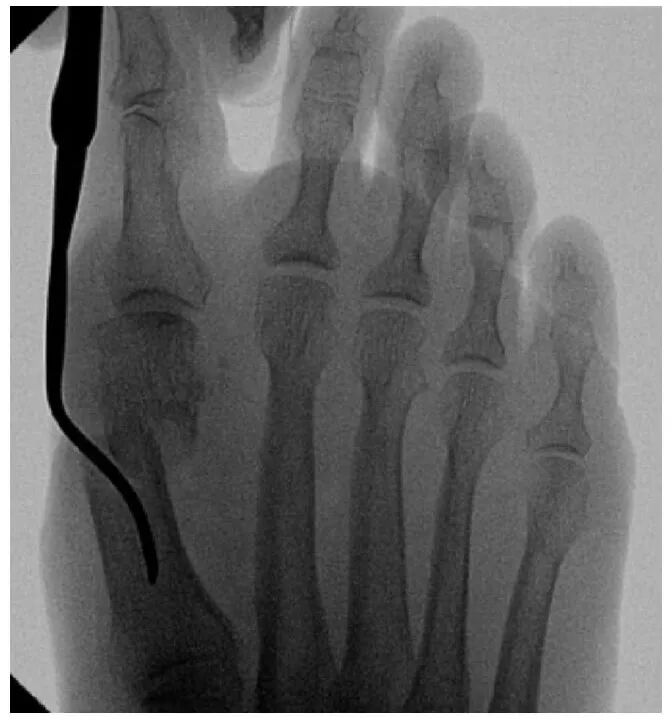

截骨完成后,将弯曲的骨膜剥离器插入截骨部位,以平移第一跖骨头。通过近节趾骨基部内侧的3毫米切口进行额外的Akin截骨术。使用一枚2毫米克氏针通过截骨端沿拇趾内侧软组织向远端穿过,从趾尖的跖内侧穿出。然后将克氏针逆行插入第一跖骨的髓管。